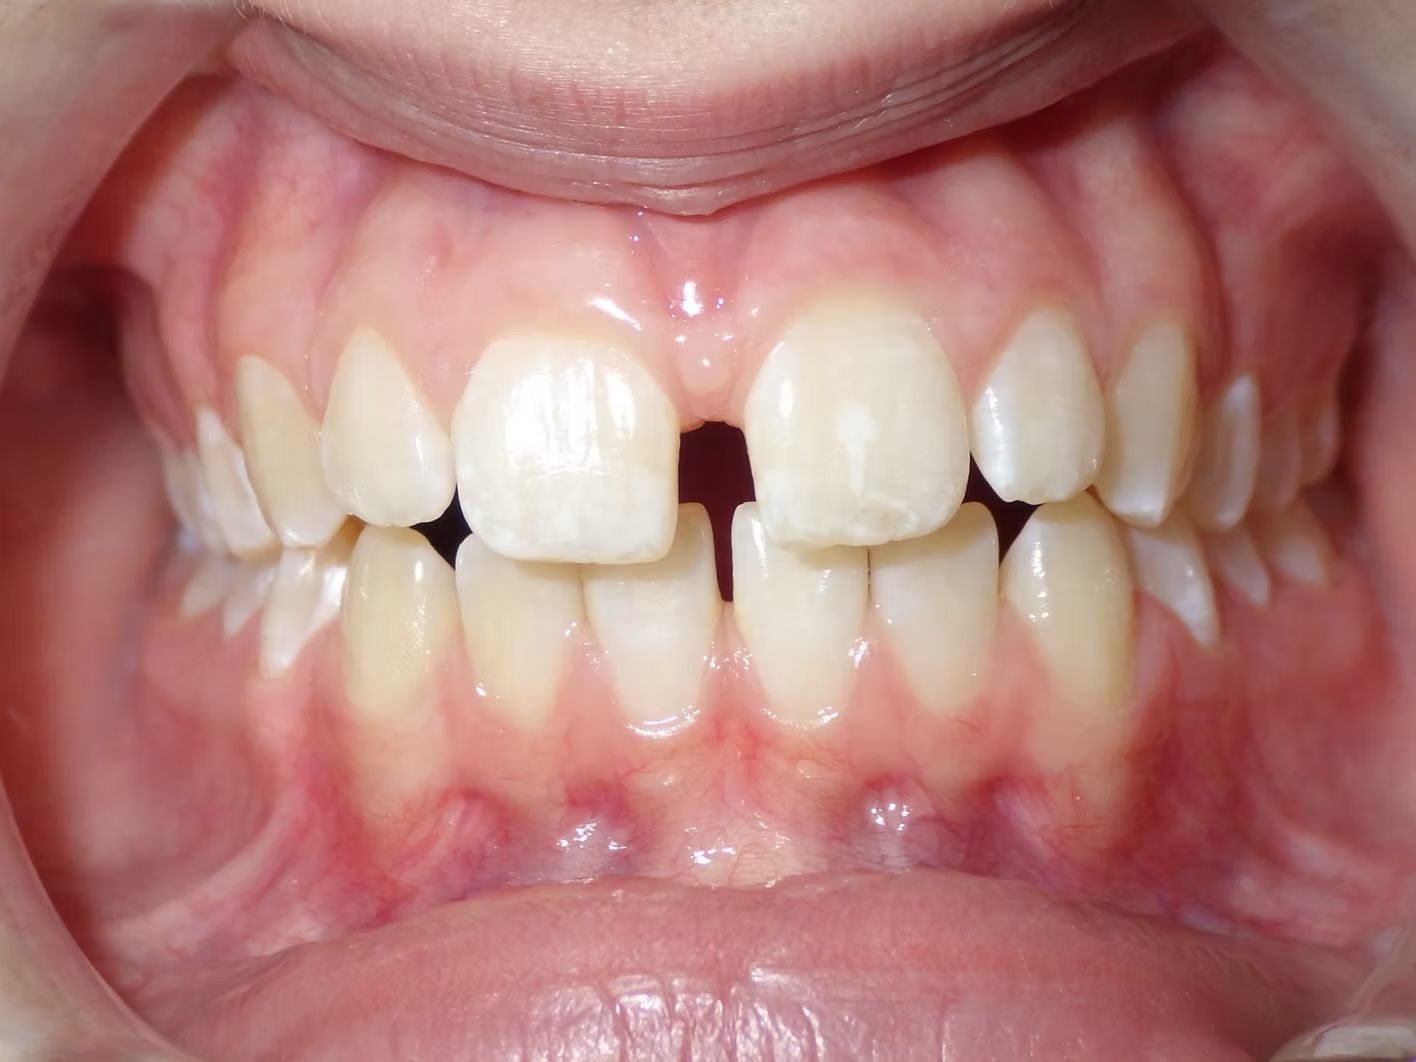

STEPHANIE

Stephanie didn't like the space between the upper teeth. Dr Freedman was able to close the space and complete her treatment in less than 20 months and her teeth remain beautiful in retention. She has a fixed (permanent) retainer behind her front teeth.